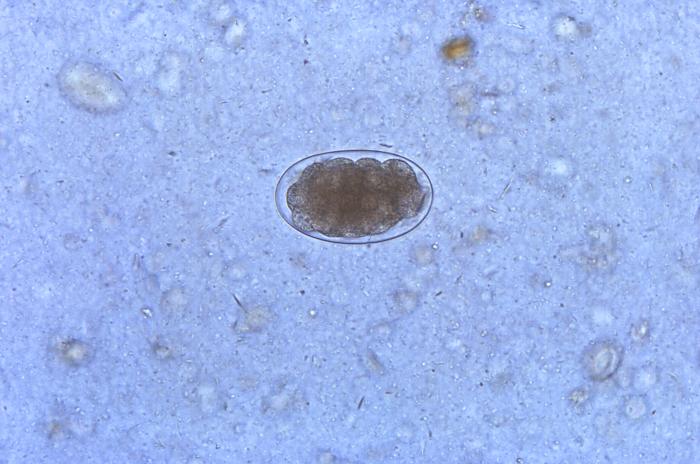

Los huevos tienen forma oval, con una cubierta fina y un tamaño de 56-76 micras (μm) por 35-47 μm.